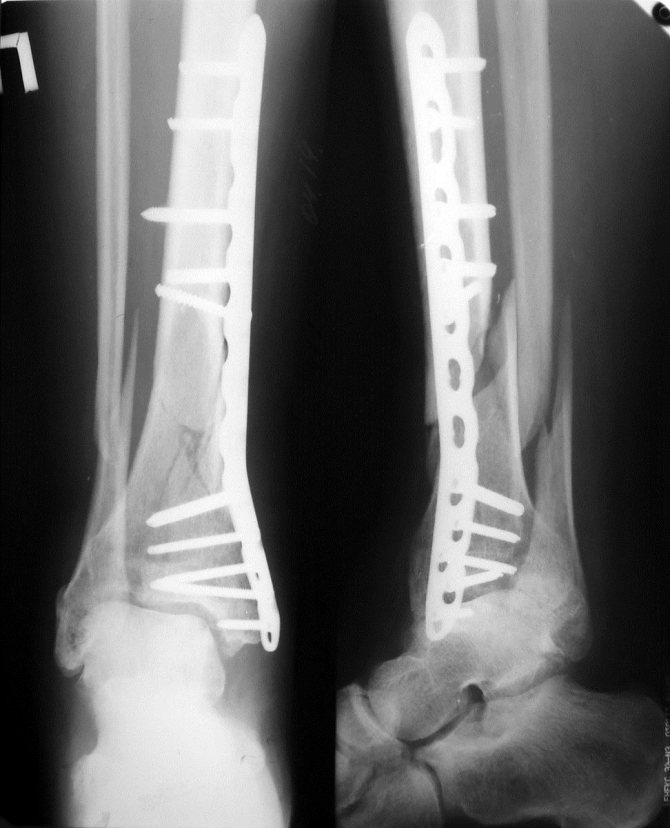

- Ограничение подвижности сустава, рядом с которым установлена металлоконструкция. Например, пластина на голени вблизи голеностопного сустава.

- Смещение с места установки или повреждение металлоконструкций. При контрольной рентгенографии может обнаружится репозиция импланта или его повреждение, в таком случае проводится операция по его замене.

- Снятие позиционного болта на лодыжке спустя 6—8 недель после установки импланта в ноге.

Процедура снятия металлоконструкций

Операция по удалению имплантов является несложной, при условии их корректной установки. Удаление спиц происходит под местным обезболиванием, путем скусывания и выкручивания стержней. Пластины удаляют под общей, спинальной или местной анестезией. Затем рассекается кожа, зачастую в том же месте где и первый раз, и происходит выкручивание винтов, снятие пластины. При удалении штифта устанавливающегося в трубчатые кости, например остеосинтез голени при поперечном переломе, извлекается стержень и крепежный винт. Такая операция занимает порядка 30 минут.

Операция с пластиной при переломе голени со смещением проводиться в несколько этапов:

- скрытие места перелома;

- очистка места перелома от сгустков крови, мягких тканей и костных отломков, которые мешают вправлению костей;

- металлостеосинтез (установка пластины и фиксация ее шурупами);

- рентгеновский снимок для контроля;

- послойное ушивание раны;

- наложение гипсовой лангеты.

В процессе операции операционное поле промывается несколько раз, чтобы в открытые ткани не попала инфекция. Вдоль пластины укладывается резиновый или трубчатый дренаж, который позволяет выводить из раны скопившуюся кровь (предотвращение образования гематомы). На операционную рану накладывается стерильная повязка.

Металлоостеосинтез большеберцовой кости пластиной